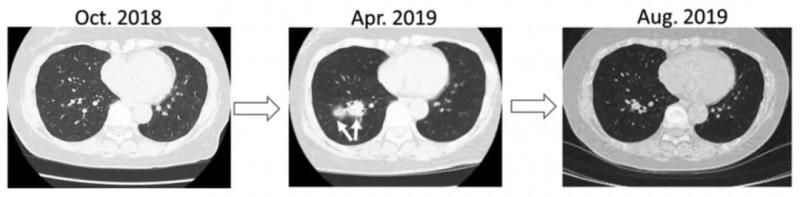

病例8(64岁女性尿路上皮癌肺转移患者)

该患者于2015年出现双肺转移,2018年8月病灶增大后用帕博利珠单抗,2019年4月因自身免疫性垂体炎停药,并姑息治疗;2019年5月起接受新抗原肽脉冲DC疫苗淋巴结内输注。

结果显示:2019年7月复查CT显示,肺转移灶明显减少(详见下图)。同年11月结束6次疫苗治疗后,恢复补充皮质醇的派姆单抗治疗。截至2021年3月,患者病情稳定、体能良好。